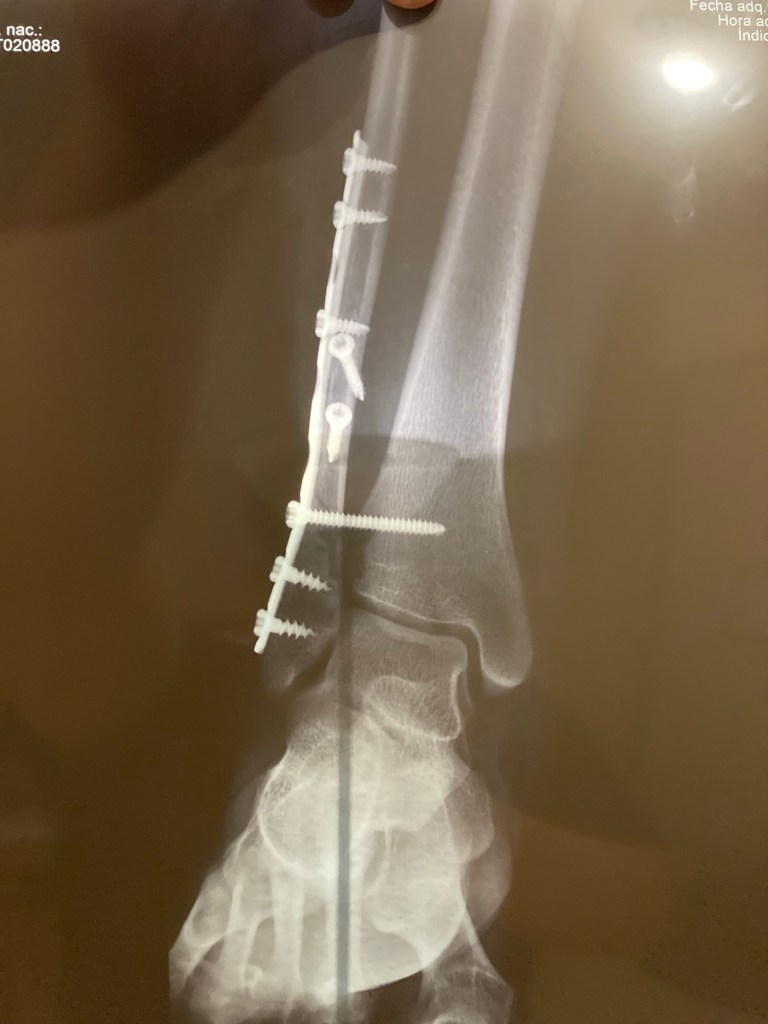

Y como bien dice el dicho: “Una imagen dice más que mil palabras”, dejaré de escribir y mejor te mostraré el resumen gráfico del blue monday de mi familia:

¿Pero qué crees? No nos sentimos “blue” (tristes), nos sentimos agradecidos porque todo salió bien, y todo saldrá bien. ¿Cómo lo sé? Porque todo diciembre estuve recordando que “Dios está de mi lado”, y un Blue Monday no cambiará eso. 😎